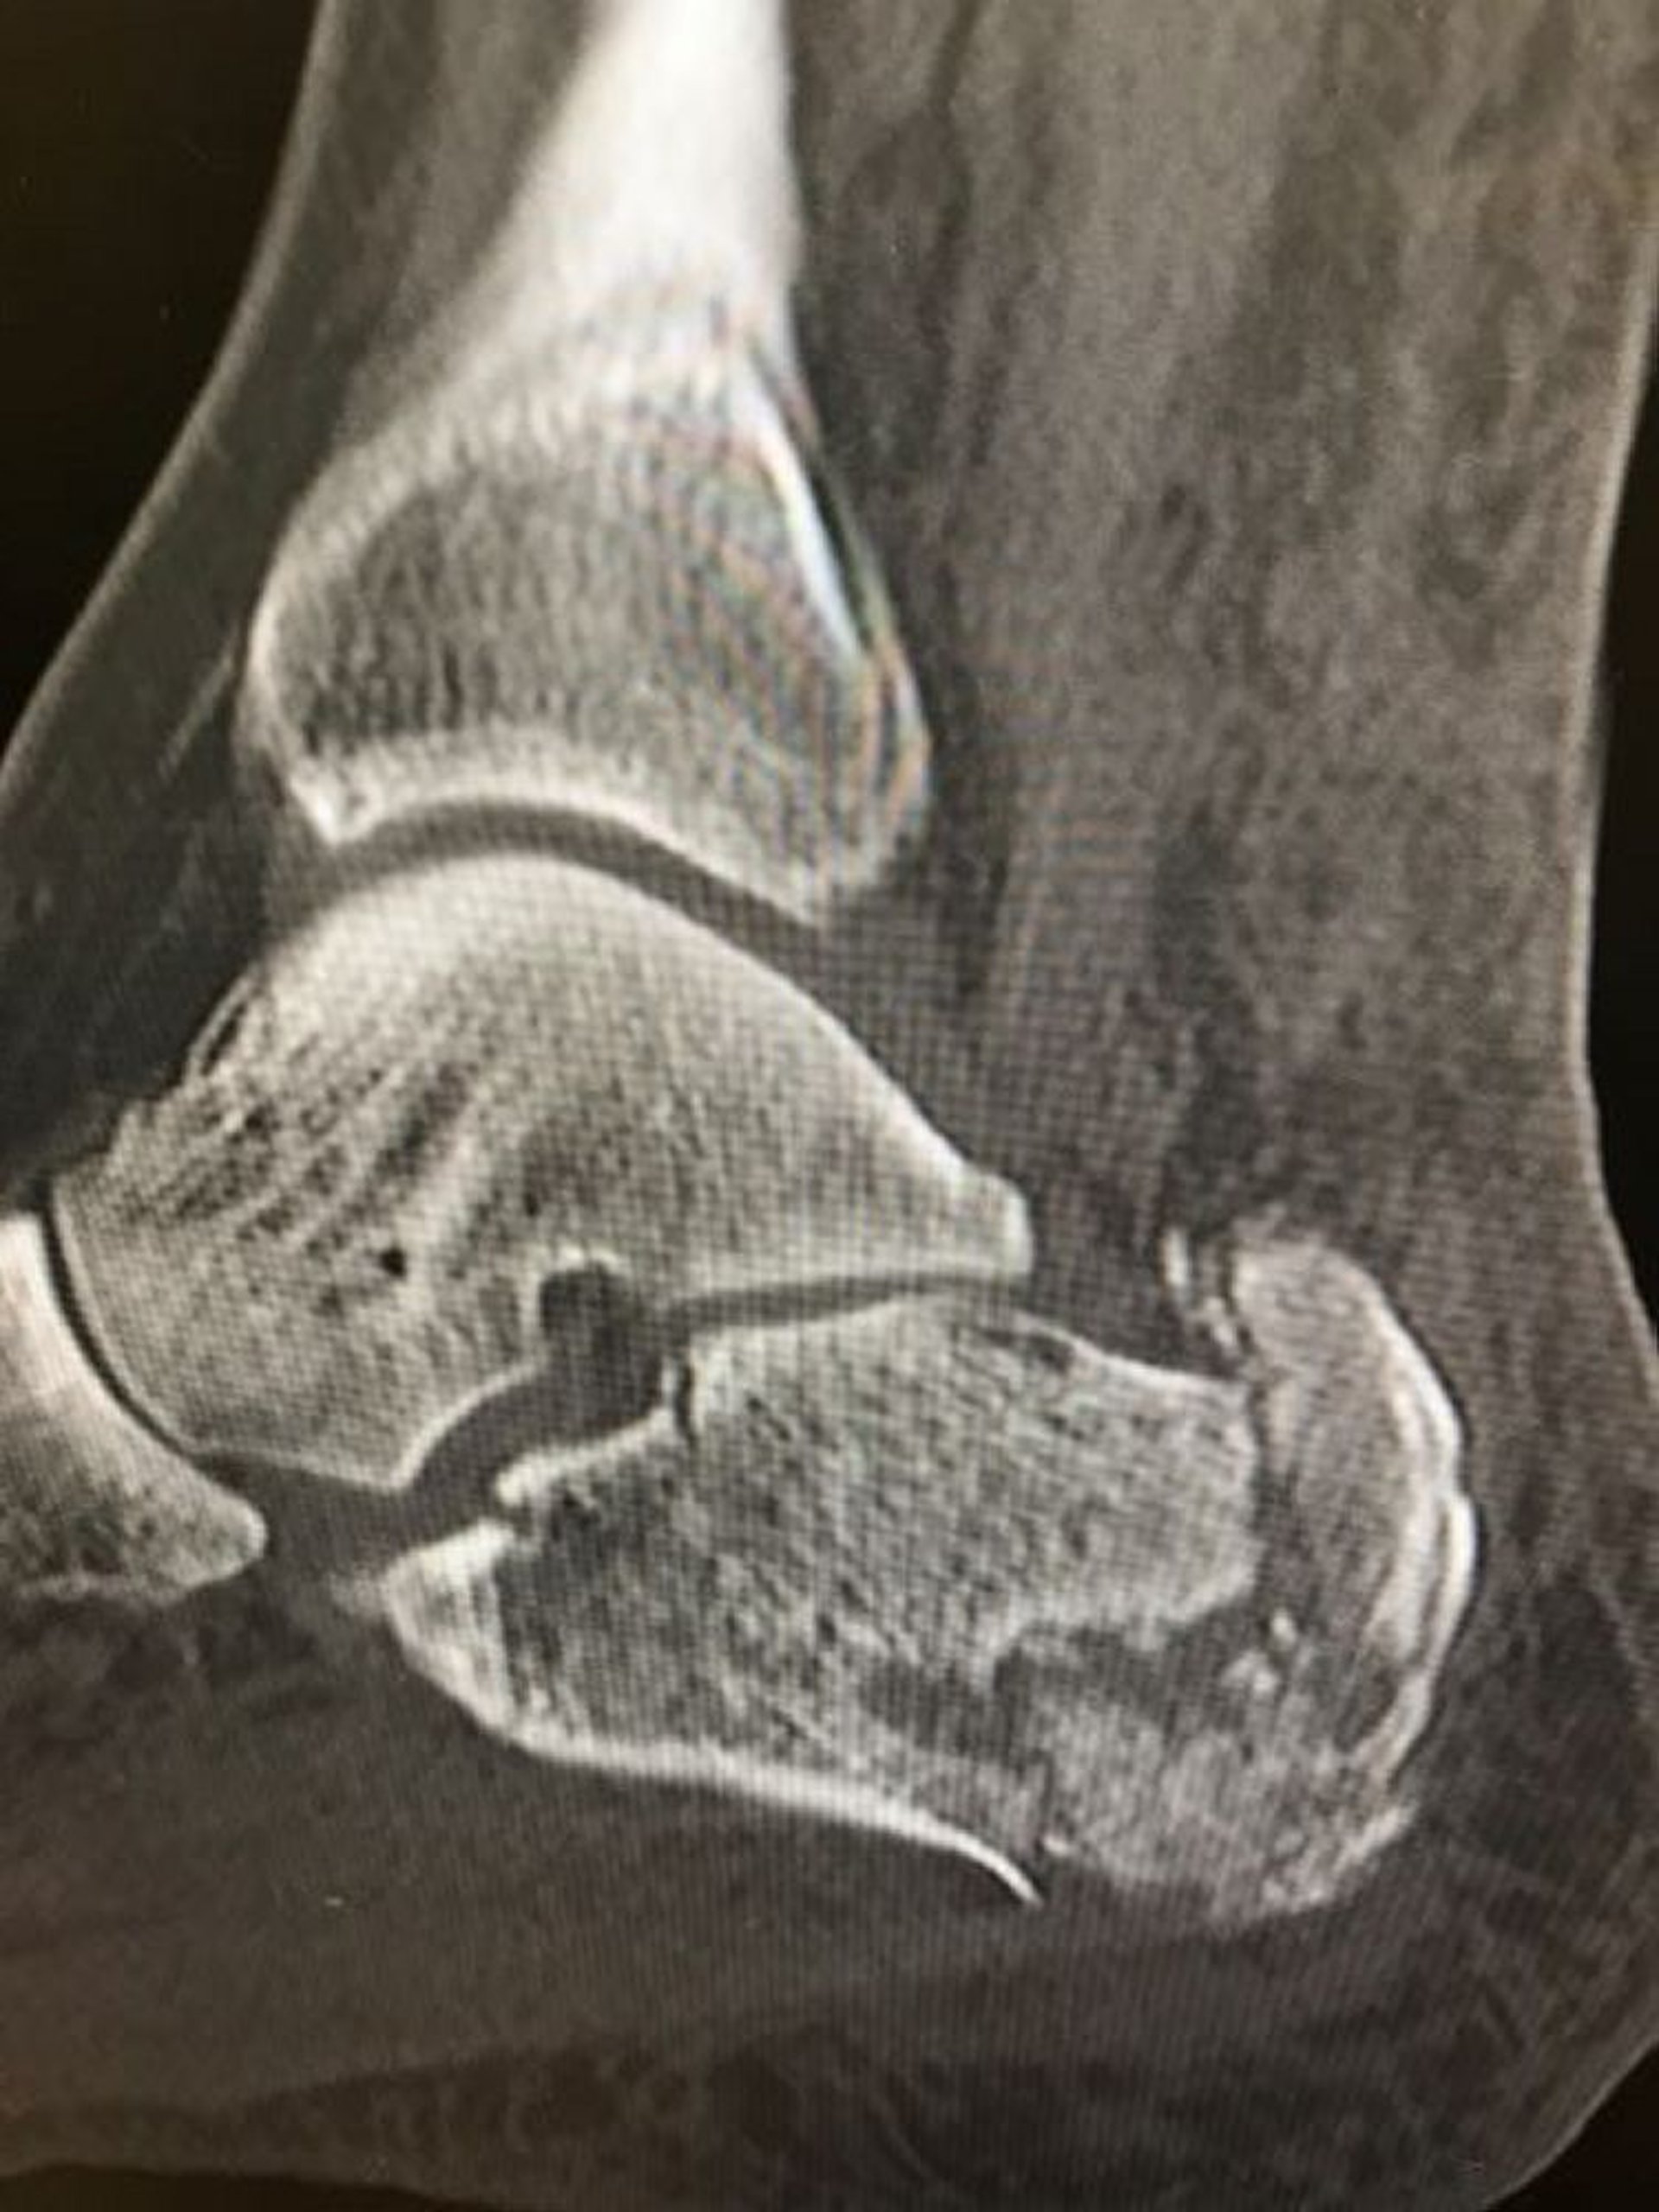

Esta radiografía muestra una fractura conminuta del calcáneo.

Image courtesy of Danielle Campagne, MD.